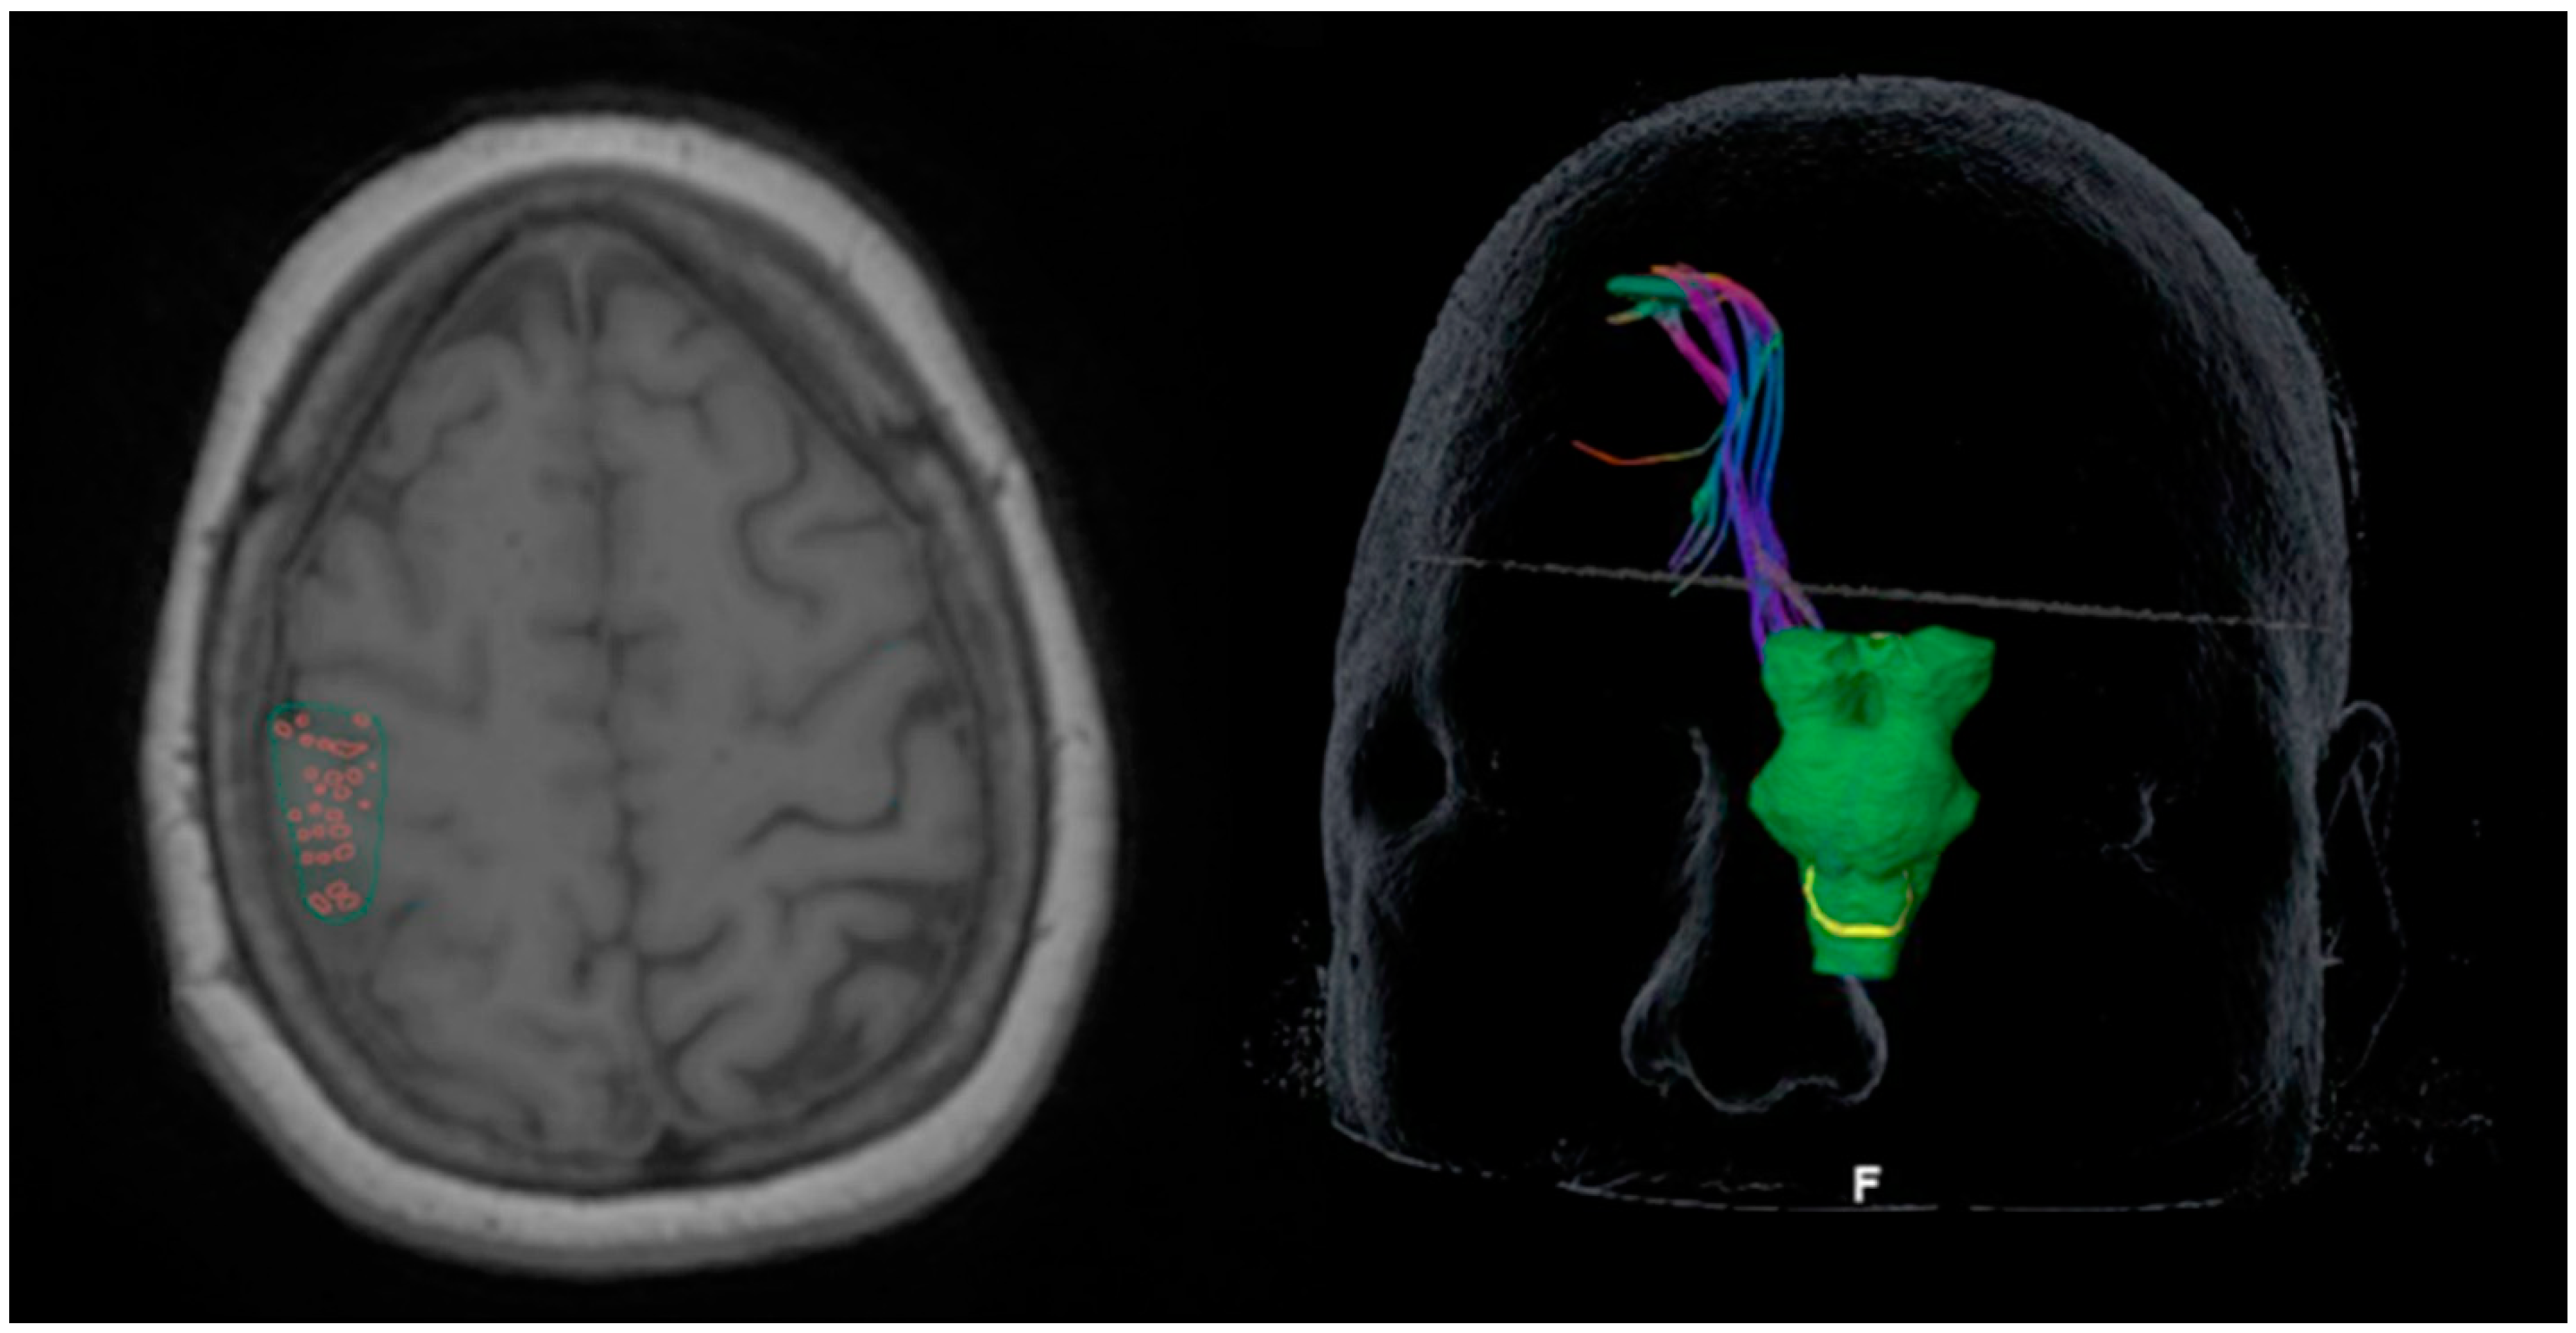

2.2. Diffusion Tensor Imaging

2.3. Perioperative Overlays